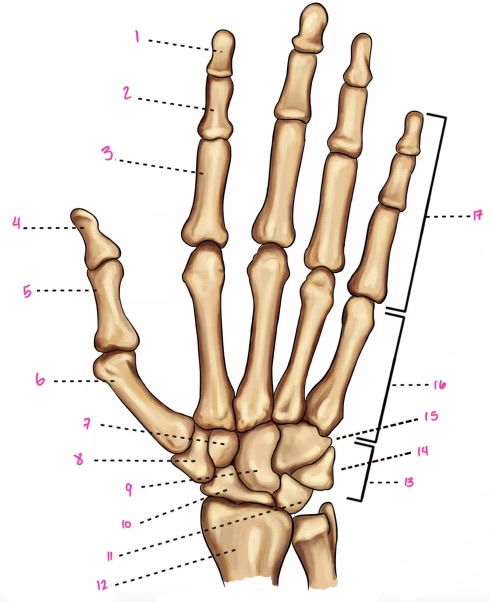

1

1

2

2

3

3

4

9

5

10

6

11

7

14

8

15

9

16

10

17

11

18

12

1

13

2

14

3

15

4

16

5

17

6

18

7

19

8

20

9

7

22

8

23

9

24

10

25

11

26

13

27

14

28

15

29

16

30

17

Phalanxes